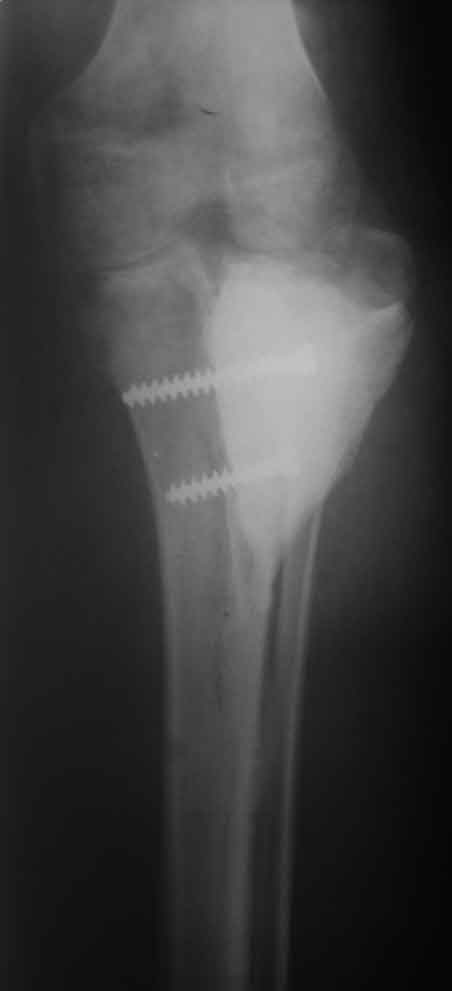

Костный и мягкотканый дефект голени

Рентген, интраоперационные фото и после снятия повязки